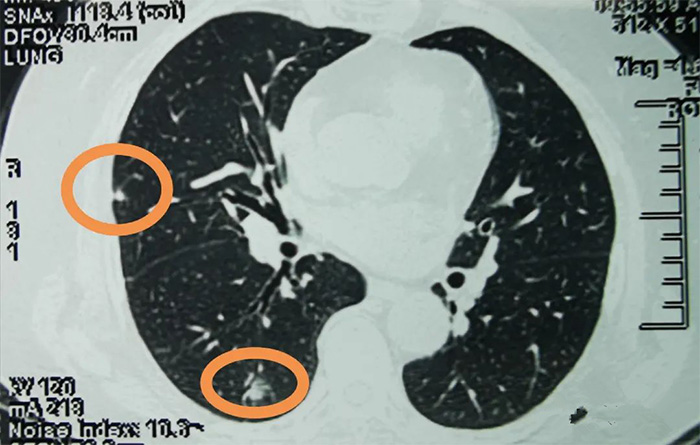

这是患者的胸部CT,被黄色圆圈标记的就是右肺的两个结节。医生在看完CT片后说这两个结节从影像学上来看,不能除外恶性,建议再做一个“肺小结节自身抗体检测”评估结节是否激发肿瘤免疫反应。

化验结果报告提示自身抗体个别指标明显升高,检测结果为阳性,患者的肿瘤免疫系统已经被激发,结节生物特性活跃,细胞的增殖速度与侵袭能力更强,也就是结节有继续长大的趋势。这个结节两个维度评估都是阳性,恶性概率很高,建议尽快手术。

2020年4月17日,这位患者在我院胸外科行手术治疗,术后病理报告显示两个结节均为肺癌。